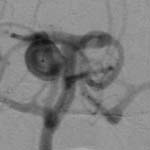

³úµ¿¸Æ·ù¿¡

ÀÇÇÑ ÁöÁÖ¸·ÇÏÃâÇ÷ÀÇ CT¼Ò°ß ¹× Ç÷°üÁ¶¿µ¼ú¿¡¼

Àü±³Å뵿¸Æ¿¡ µ¿¸Æ·ù°¡ º¸À̰í ÀÖ´Ù.

<¼ö¼ú

Àå¸é> <¼ö¼ú

ÈÄ>

¼ö¼ú

ÈÄ µ¿¸Æ·ù°¡ º¸ÀÌÁö ¾ÊÀ¸¸ç µ¿¸Æ·ù °æºÎ¿¡

Ŭ¸³ÀÌ µé¾î°¡ ÀÖ´Â °ÍÀÌ º¸À̰í

ÀÖ´Ù.